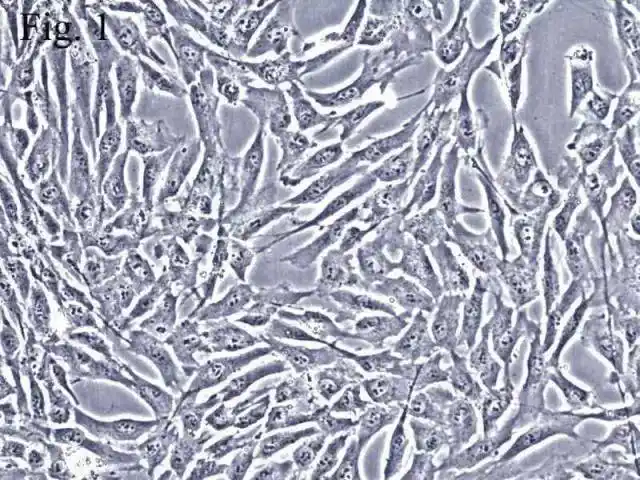

【求助】我的sd大鼠msc(骨髓间充质干细胞)状态如何

【讨论】小鼠骨髓间充质干细胞形态(有很多图片!希望高手们参与讨论)